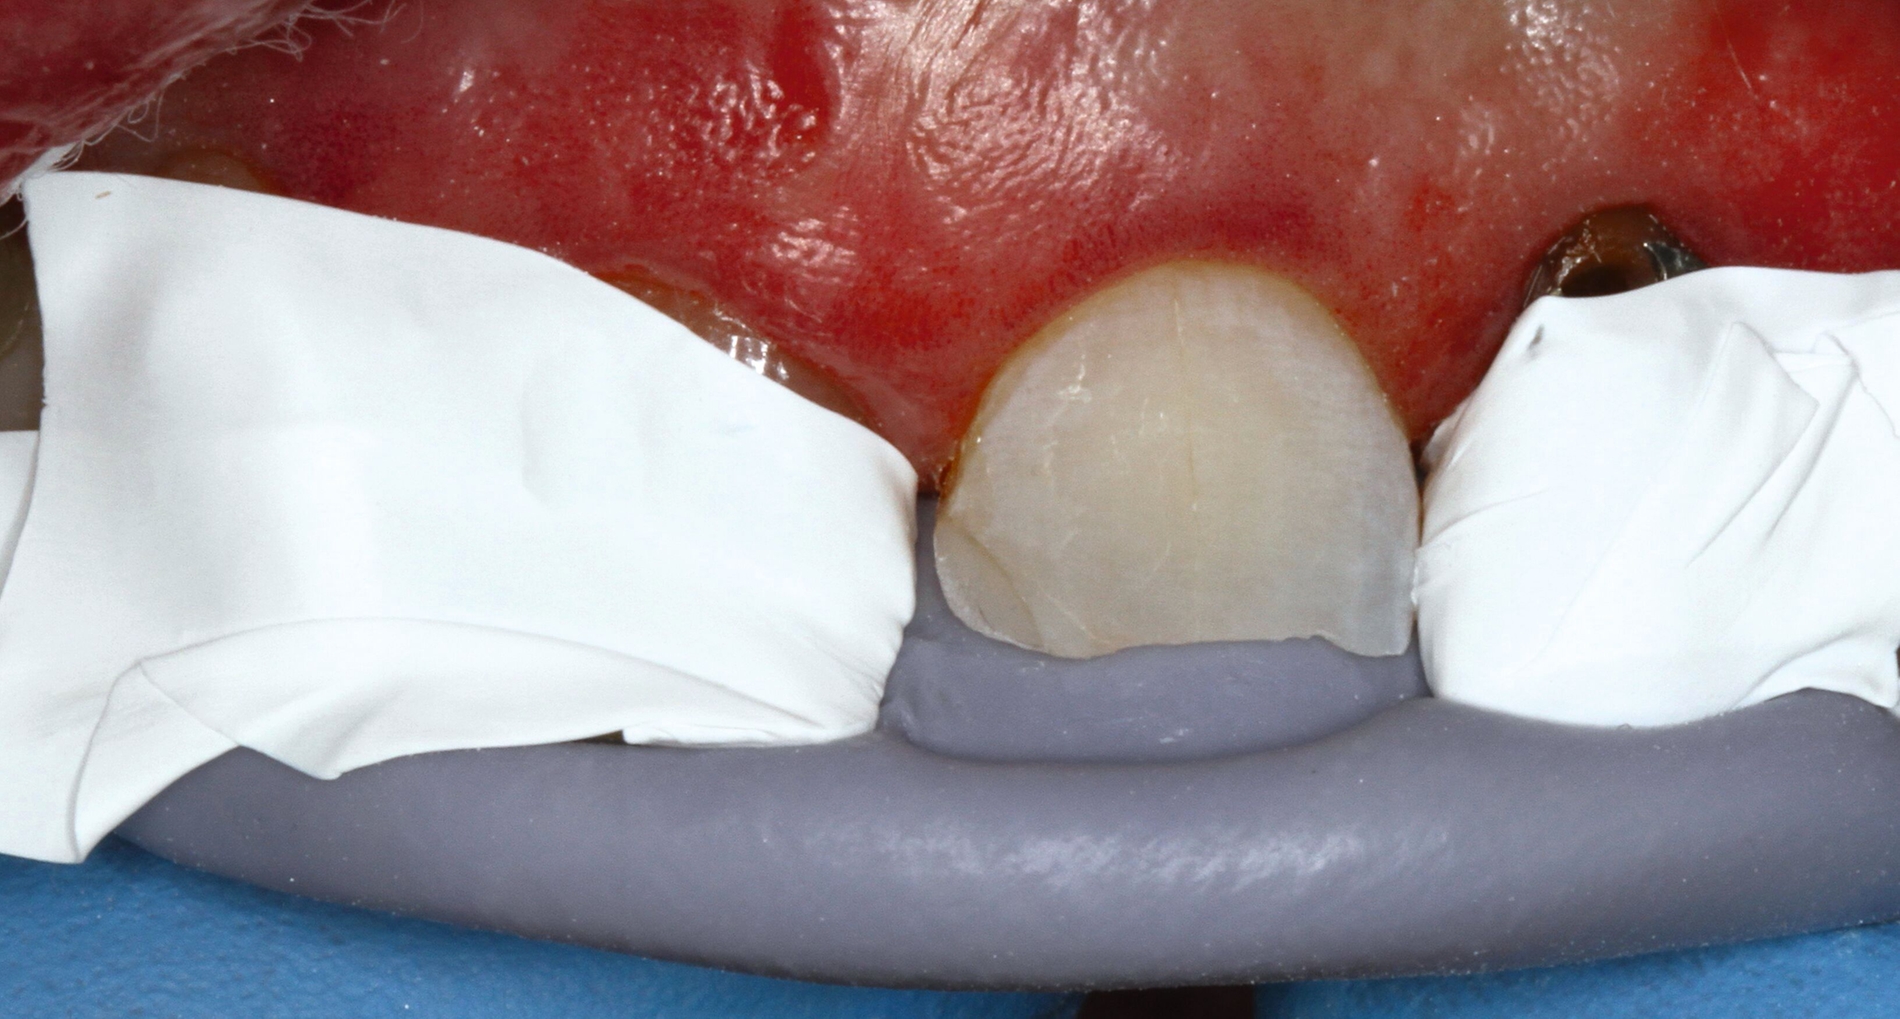

Vor 25 Jahren hatte der Patient ein Frontzahntrauma an Zahn 22 erlitten, der daraufhin mit einer Wurzelspitzenresektion und einer retrograden Amalgamfüllung versorgt worden war (Abbildung 3a). Dabei war die Zahnkrone mit einer keramisch verblendeten Stiftkrone aus Nichtedelmetall rekonstruiert worden, die nun aufgrund von Sekundärkaries insuffizient und gelockert war, jedoch keine Beschwerden verursachte. Klinisch wies der Zahn eine sehr kurze klinische Krone ohne ausreichendes Ferruledesign auf (Abbildung 5a) [Naumann et al., 2018a; Naumann et al., 2018b]. Neben dem Verdacht auf einen obliterierten mittleren Wurzelkanalabschnitt gab es röntgenologisch keinen Hinweis auf apikale Osteolysen oder parodontale Auffälligkeiten (Abbildung 3b). Der Patient entschied sich trotz des erhöhten Zahnhartsubstanzdefekts für den Zahnerhalt durch einen adhäsiv verankerten Kompositaufbau.

Für die restaurative Therapie von Zahn 22 wurde die alte Stiftkrone entfernt und die Stiftbohrung an die neue Indikation angepasst (Abbildungen 5a und 5b). Die Zahnkrone wurde dabei in drei Phasen wiederhergestellt: adhäsives Zementieren eines konfektionierten Glasfaserstifts, Stumpfaufbau und Modellation einer direkten Kompositkrone mit Silikonschlüssel, Frontzahnmatrize für komplexe Situationen und Schneepflugtechnik (Abbildungen 5c bis 5e) [Urkande et al., 2023; Amaro et al., 2021; Frese, 2020; Mannocci et al., 2002; Dimitrouli et al., 2011; Opdam et al., 2003]. Im Röntgenkontrollbild zeigt sich ein suffizienter Stiftaufbau (Abbildung 6).